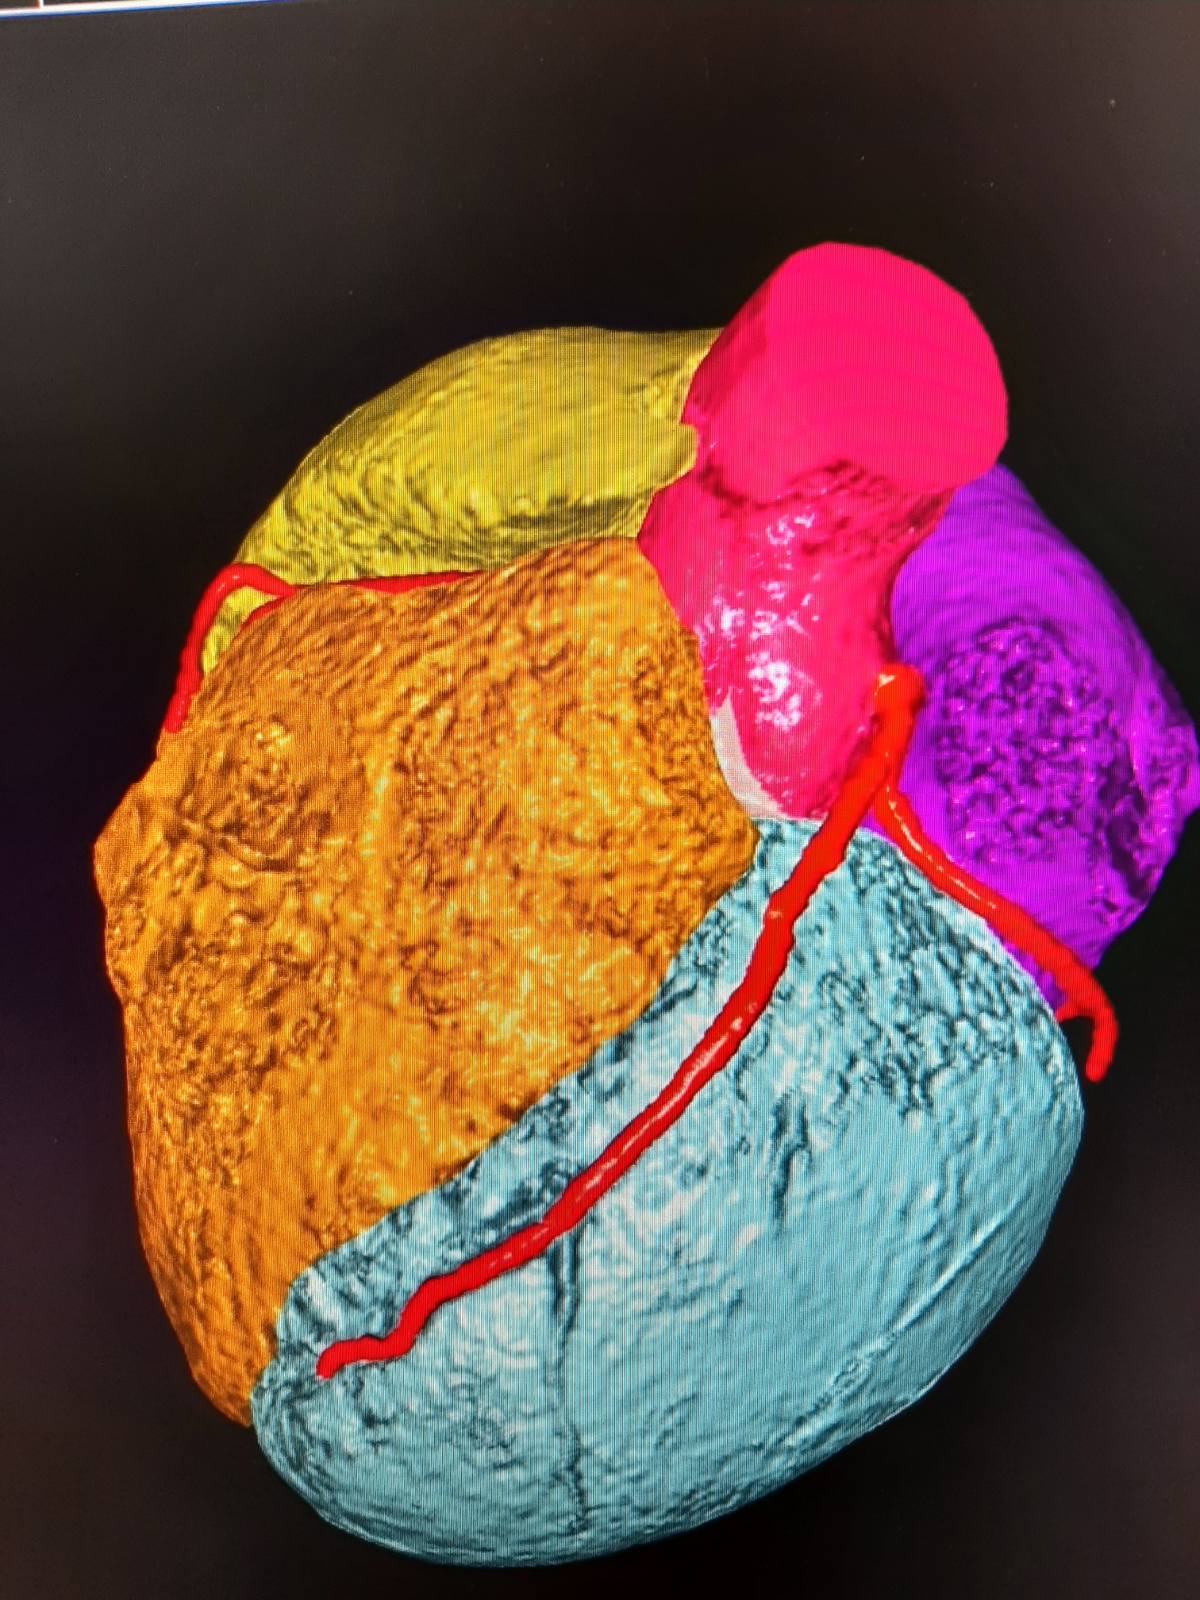

MSCT koronarografija predstavlja minimalno invazivnu pretragu koja omogućuje precizno snimanje srca i njegovih krvnih žila u svega nekoliko sekundi

MSCT koronarografija predstavlja minimalno invazivnu pretragu koja omogućuje precizno snimanje srca i njegovih krvnih žila u svega nekoliko sekundi. Ova napredna metoda koristi rendgensko zračenje i kontrastno sredstvo za iznimno točno otkrivanje ili isključivanje aterosklerotskih promjena – glavnog uzroka srčanog udara i drugih kardiovaskularnih bolesti.

Uvođenjem MSCT koronarografije, Županijska bolnica Čakovec svrstava se među malobrojne zdravstvene ustanove u Hrvatskoj koje posjeduju tehničke i kadrovske kapacitete za izvođenje ove napredne pretrage. Tehnologija koja je do nedavno bila rezervirana za velike kliničke centre sada je dostupna i pacijentima u sjeverozapadnoj Hrvatskoj.